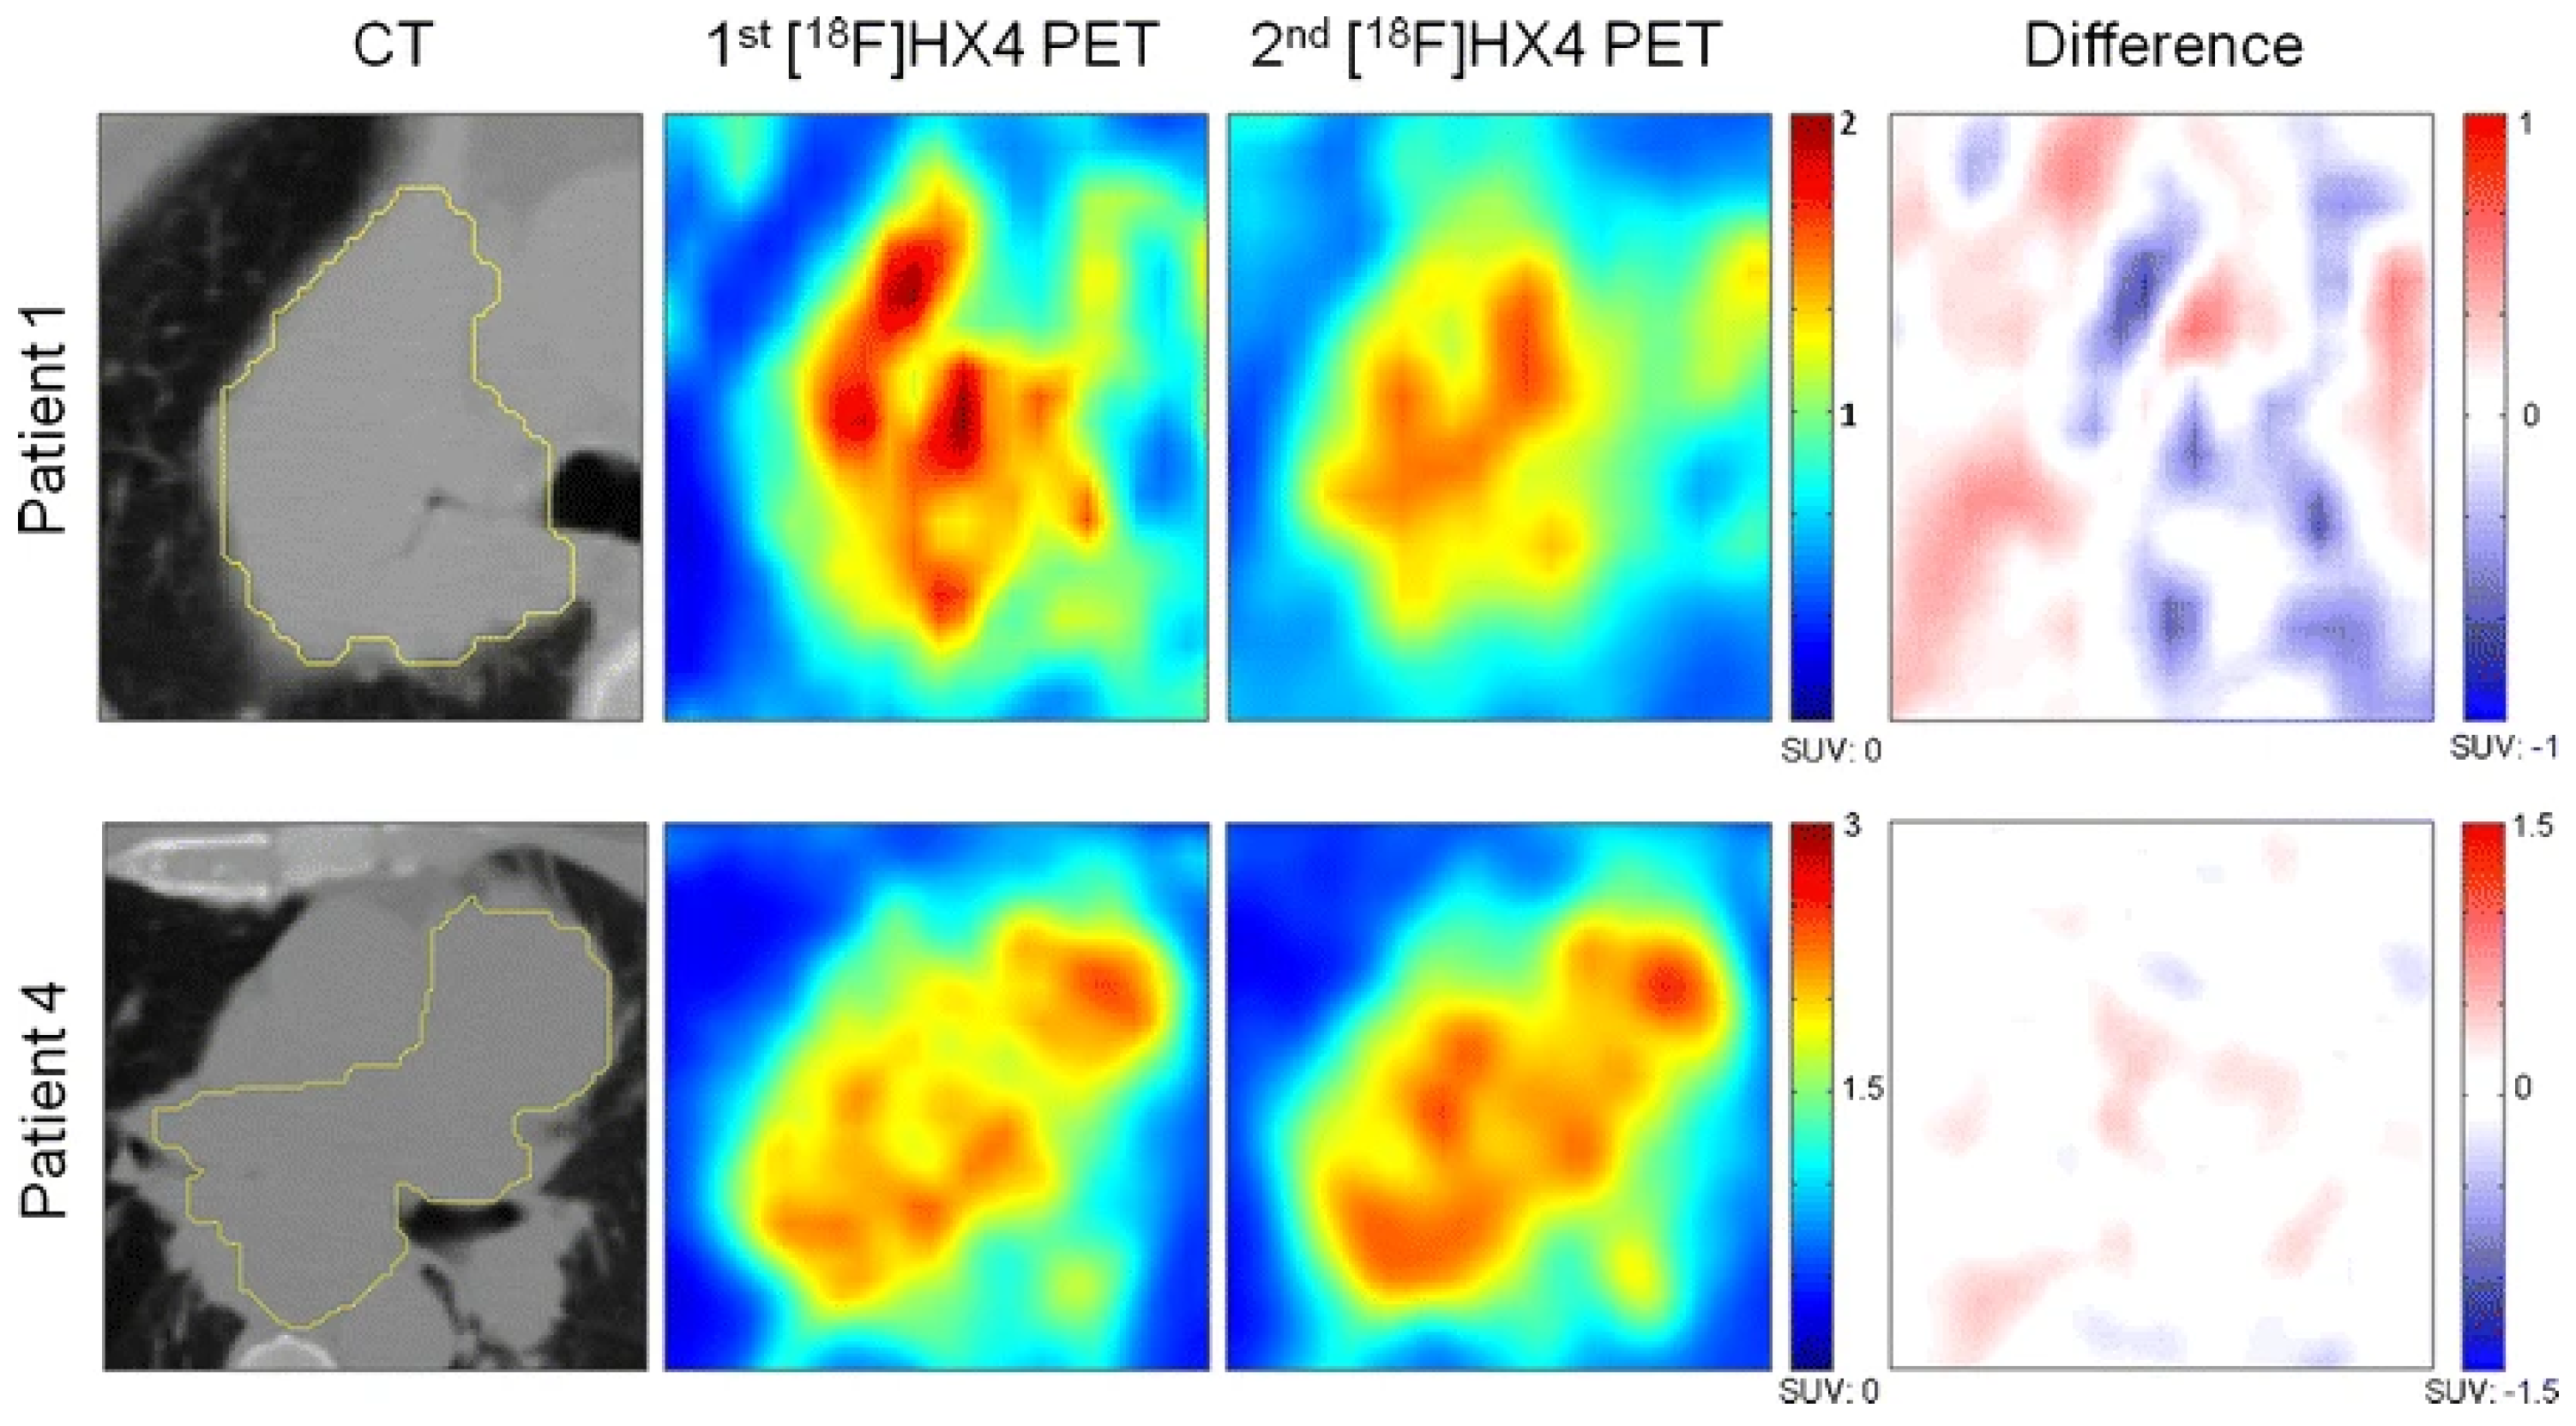

- Sanduleanu, S.; Wiel, A.M.A.V.; Lieverse, R.I.Y.; Marcus, D.; Ibrahim, A.; Primakov, S.; Wu, G.; Theys, J.; Yaromina, A.; Dubois, L.J.; et al. Hypoxia PET Imaging with [18F]-HX4-A Promising Next-Generation Tracer. Cancers 2020, 12, 1322. [Google Scholar] [CrossRef]

- Zegers, C.M.L.; van Elmpt, W.; Wierts, R.; Reymen, B.; Sharifi, H.; Öllers, M.C.; Hoebers, F.; Troost, E.G.C.; Wanders, R.; van Baardwijk, A.; et al. Hypoxia imaging with [18F]HX4 PET in NSCLC patients: Defining optimal imaging parameters. Radiother. Oncol. 2013, 109, 58–64. [Google Scholar] [CrossRef]

- Zegers, C.M.L.; van Elmpt, W.; Szardenings, K.; Kolb, H.; Waxman, A.; Subramaniam, R.M.; Moon, D.H.; Brunetti, J.C.; Srinivas, S.M.; Lambin, P.; et al. Repeatability of hypoxia PET imaging using [18F]HX4 in lung and head and neck cancer patients: A prospective multicenter trial. Eur. J. Nucl. Med. Mol. Imaging 2015, 42, 1840–1849. [Google Scholar] [CrossRef]